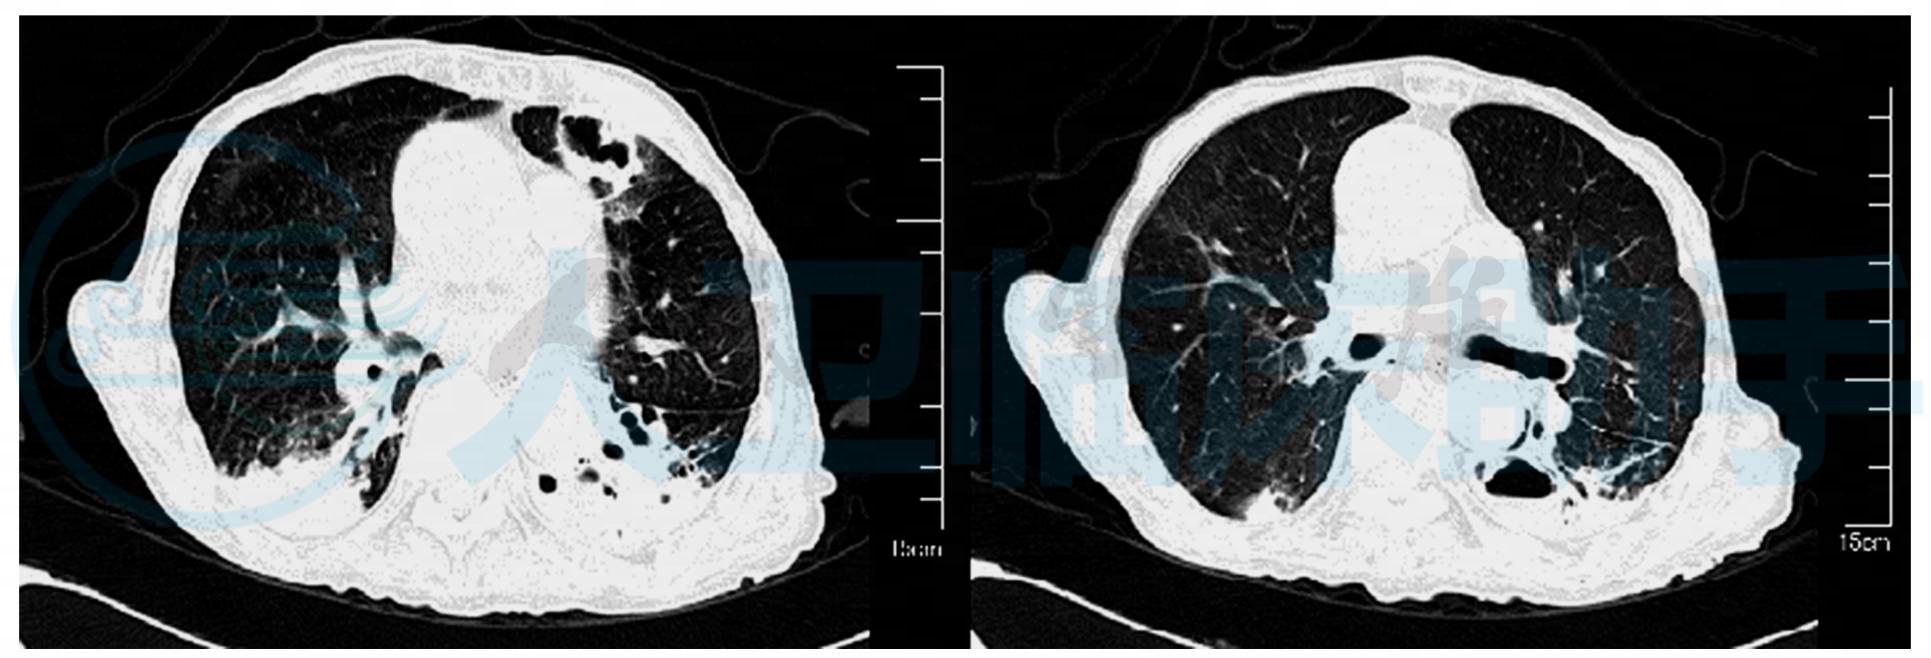

入院时辅助检查:血常规:白细胞:10.5×109/L,中性粒细胞百分比:97.7%,红细胞:4.5×109/L,血红蛋白:148g/L,血细胞比容:44%,血小板:72×109/L。肝肾功:总蛋白:49.3g/L,白蛋白:22.6g/L,白球比:0.8,谷丙转移酶:21U/L,谷草转移酶:16U/L,总胆红素:18.1μmol/L,直接胆红素:7.7μmol/L,间接胆红素:10.4μmol/L。尿素:30.96mmol/L,肌酐:174μmol/L。尿常规:尿蛋白:+,酮体:微量。镜检项目:红细胞:35.92/μl,管型:29.63/μl。凝血五项:纤维蛋白原含量:5.2g/L。脑钠肽:61.0pg/ml。肺炎支原体抗体:阴性。肌钙蛋白I:0.03ng/ml。心肌酶谱:肌酸激酶:124U/L,肌酸激酶MB同工酶:9U/L。血气分析:pH:7.462,二氧化碳分压:25.7mmHg,氧分压:62mmHg,实际碳酸氢盐:18.3mmol/L,标准碳酸氢盐:19.7mmol/L,二氧化碳总量:19mmol/L,细胞外液剩余碱:-5mmol/L,钾离子:5.4mmol/L。肺CT(图1):双肺渗出病变,左肺下叶大部分肺组织实变,左侧胸膜增厚、钙化。心电图:窦性心动过速,T波高耸。

图1 双肺渗出病变,左肺下叶大部分肺组织实变,内见透光,左侧胸膜增厚、钙化

入院第24天(2010年11月25日)患者仍咳痰费力不能自主排痰,查体:T:37.5℃,BP:126/71mmHg,HR:82次/分,RR:20次/分,神志淡漠,背部皮肤可见数个散在凸出皮肤表面,类椭圆形红色丘疹,触之质韧。双肺可闻及干湿啰音,可闻及痰鸣音,心律齐,双下肢无水肿。肺CT(图2):双肺实变影增多,左肺上叶新发空洞,内壁不光滑,左肺下叶实变影的透光病变形成液平。复查血常规、痰血细菌真菌培养等相关化验检查,完善气管镜检查,加用醋酸卡泊芬净(科赛斯)抗感染治疗。皮肤科印诊:多形红斑?应用低敏片及复方甘草酸苷胶囊口服,氢定乳膏外用治疗。

图2 双肺实变影增多,左肺上叶新发空洞,内壁不光滑,左肺下叶实变影的透光病变形成液平